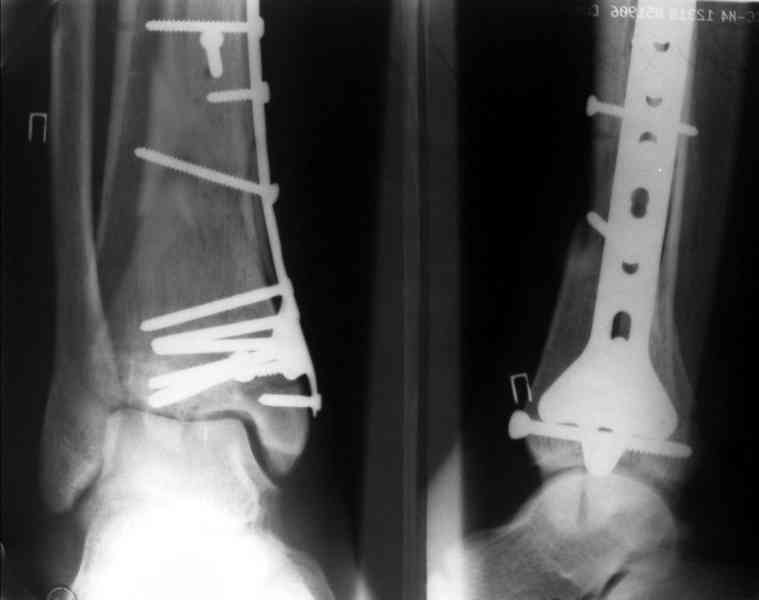

Посмотрим вроде прошло если понравится напишите расскажу как это сделать.По принципам АО кстати при поступлении сначала восстанавливают длину малоберцовой кости фиксируют пластиной 1/3 трубки потом накладывают аппарат наружной фиксации и через 7-10 дней открыто восстанавливают большеберцовую кость.С уважением Дрягин

На рентгенограммах типичный перелом пилона по типу С-3. есть опыт до 100 открытых опреаций у нас в клинике. 20 примерно в год. Принцип один -все внутрисуставные переломы нуждаются в открытой репозиции и внутренней стабильной фиксации. При поступлении КТ не надо, так как получается только нагромождение костей. Истинной картины нет. Главное восстановить длину малоберцовой кости - это ключ к успеху. При поступлении меньше всего надо думать о сосудистых расстройствах, т.к. сама операция и репозиция даже сначала частичная даёт улучшение сосудитых нарушений. Причём очень быстро. Операция в 2этапа. При поступлении доступ позади наружной лодыжки, причём обязательно. После этого репозиция малоберцовой кости и фиксация пластиной 1/3 трубки под винт 3,5. Дренаж и любой аппарат наружной фиксации. Затем после спадения отёка на 5-7-10 день аппрат снимается и дугообразный разрез спереди от медиальной лодыжки 10-12 см. Главной чтобы расстояние между 1 и вторым разрезом было не меньше 7-8 см. Тогда не будет некрозов лоскутов. Таранная кость используется как матрица на неё укладываются отломки и фиксируются пицами. Ренг-контроль. Отломки лежат все отдельно, но ничего не высыпется. При переломах С-3 всегда нужна костная пластика (из крыла). Фиксация пластиной лист клевера простой или LCP. Гипс не нужен. Дренаж до 48 часов. Операция длится 3-4 часа обязательно без жгута. Посылаю примерно такой же случай.